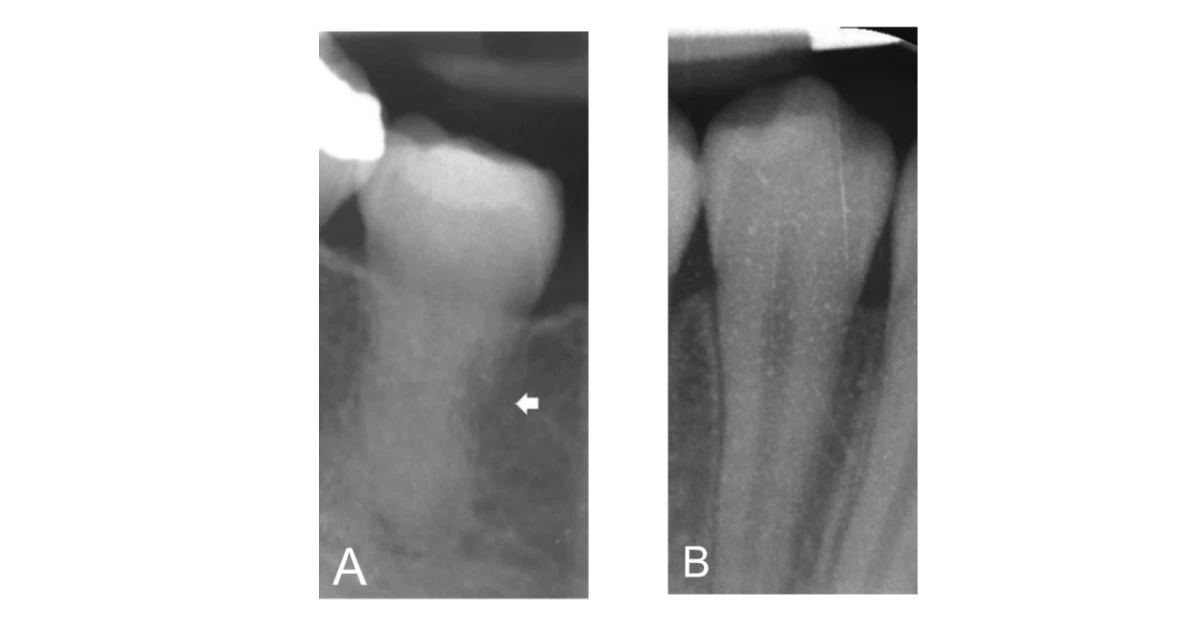

Pemeriksaan radiograf pun penting untuk menunjang diagnosis. Gambaran radiograf gigi yang mengalami tooth ankylosis ditandai dengan hilangnya garis hitam di sekitar akar gigi. Ada juga tanda hilangnya batas antara akar gigi dan tulang rahang sehingga tampak menyatu.

Secara klinis, kondisi ini dapat dikenali dengan sifat gigi yang kaku dan tidak bergerak, adanya suara dentin logam saat gigi diketuk, dan pada gambaran ronsen menunjukkan hilangnya batas antara akar gigi dan tulang. Penanganannya bergantung pada usia pasien, di mana pada anak-anak diperlukan pemantauan ketat untuk mencegah gangguan tumbuh kembang rahang, sementara pada orang dewasa dapat dilakukan observasi atau pencabutan bergantung pada apakah kondisi tersebut mengganggu estetika wajah maupun fungsi kunyah.